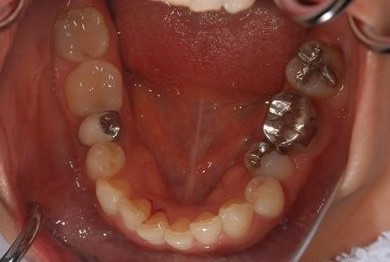

| 性別/年齢 | 女性 / 45歳 | ||||||||||||||||||||||||||||||||

| 主訴 | 右下奥虫歯による冠はずれと、前歯他冠治療済の他の虫歯の有無の確認。 | ||||||||||||||||||||||||||||||||

| 治療方針 | セラミック治療にて、審美的回復を行う。 | ||||||||||||||||||||||||||||||||

| 治療内容 | CAD/CAMオールセラミッククラウン3本(オールセラミック用土台3本)、ハイブリッドセラミックインレー2本 | ||||||||||||||||||||||||||||||||